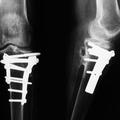

Zlomljena noga Pol stoletja z zlomljeno nogo Valižanski upokojenec je presenečen ugotovil, da je pol stoletja naokoli hodil z zlomljeno nogo.